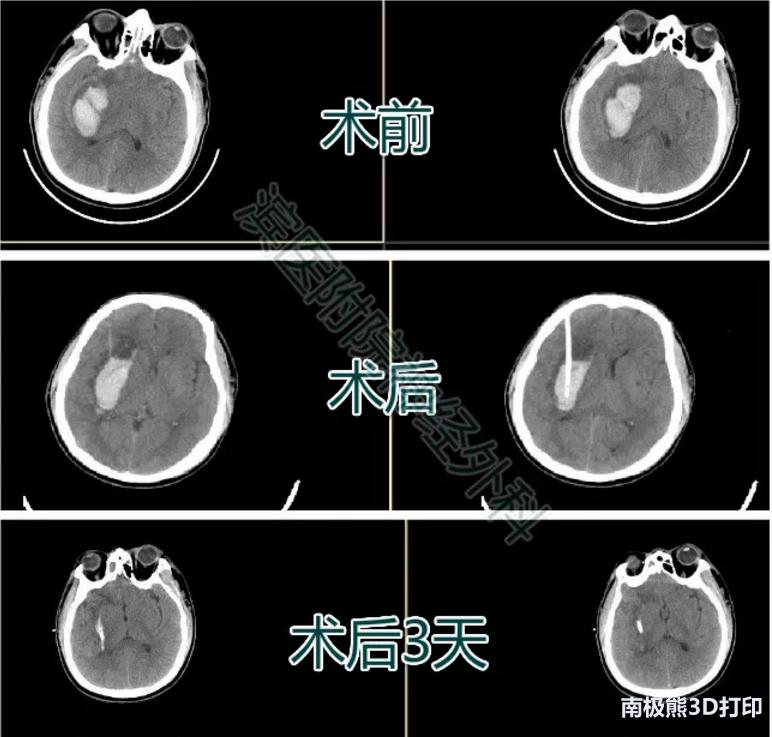

患者王某某,男,46岁,因“头痛伴左侧肢体活动不灵3天”入院。

入院查体:嗜睡状态,呼叫睁眼,言语尚可。双侧瞳孔直径约2mm,对光反应存在。左侧肢体肌力2级 ,右侧肢体肌力5级。颅脑CT示右侧基底节区脑出血。入院后排除手术禁忌,行3D导板下经额部血肿腔穿刺术,术后复查颅脑CT如图,引流管位于血肿腔中心,穿刺位置满意。辅以尿激酶血肿腔注入术后3天复查血肿已基本没有。

患者四影像资料